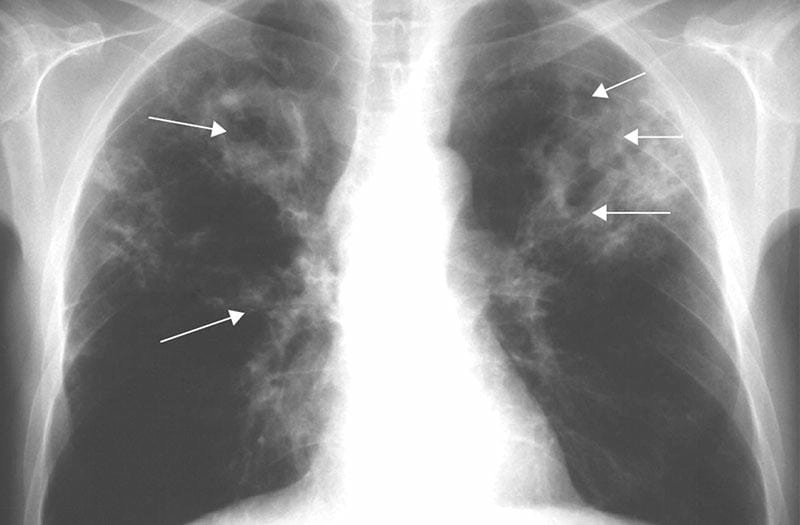

Bạn sẽ phải rùng mình khi chiêm ngưỡng hình ảnh bệnh lao phổi là như thế nào dưới ống kính y học thực tế. Những bức ảnh chụp X-quang cho thấy phổi bị tổn thương nặng, xuất hiện những đốm trắng mờ như bóng ma ám ảnh. Không chỉ là các tổn thương vật lý, đây còn là những “chứng tích sống” của căn bệnh âm thầm hủy hoại cơ thể qua từng hơi thở. Từ viêm nhẹ đến tổn thương lan rộng, hình ảnh bệnh lao phổi khiến người xem không thể rời mắt vì mức độ nghiêm trọng mà nó thể hiện rõ ràng qua từng chi tiết.

Cảnh báo: tổng hợp ảnh bệnh lao phổi chân thực này không dành cho người yếu tim. Đây là loạt hình ảnh y khoa được các chuyên gia sưu tầm và xác thực, ghi lại quá trình tiến triển của bệnh từ giai đoạn đầu đến giai đoạn nguy kịch. Từng mảng mô phổi bị ăn mòn, xơ hóa, hoại tử được phơi bày rõ nét dưới ánh sáng X-quang lạnh lùng. Những hình ảnh này không chỉ mang tính chất minh họa y học, mà còn là hồi chuông cảnh tỉnh cho bất kỳ ai còn lơ là với căn bệnh nguy hiểm này.